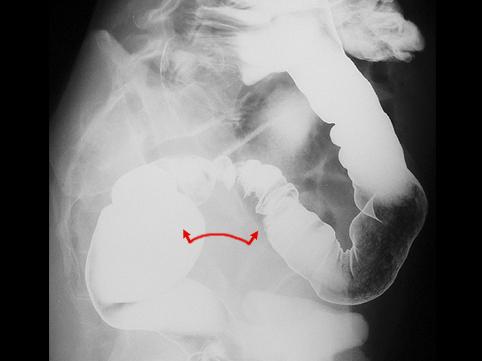

A case of intestinal endometriosis with severe stenosis of the sigmoid colon.

Tumor-like lesions/Endometriosis

Location

Large intestine(Colon)/Sigmoid colon

X-ray

40 -